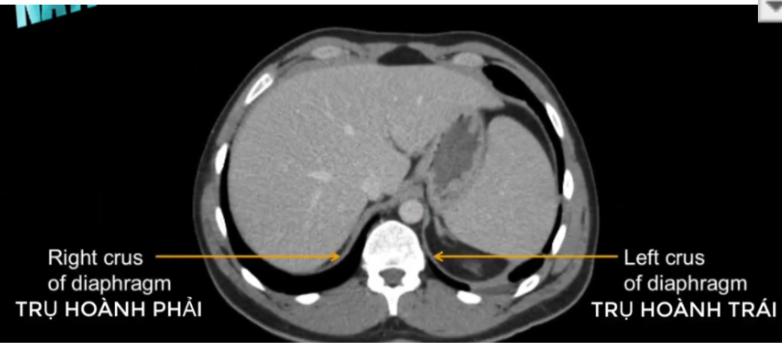

TM gan ở đâu? TM chủ dưới ? ĐM chủ?